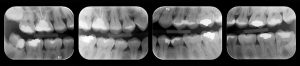

– Radiografia Interproximal